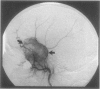

The authors present an unusual case of solitary intramedullary plasmacytoma. Awareness of this entity can facilitate appropriate surgical planning, which may include a limited biopsy prior to considering more extensive skull base surgery.